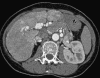

This pictorial review is based on our experience of the follow-up of 120 patients at our multidisciplinary center for hereditary hemorrhagic telangiectasia (HHT). Rendu-Osler-Weber disease or HHT is a multiorgan autosomal dominant disorder with high penetrance, characterized by epistaxis, mucocutaneous telangiectasis, and visceral arteriovenous malformations (AVMs). The research on gene mutations is fundamental and family screening by clinical examination, chest X-ray, research of pulmonary shunting, and abdominal color Doppler sonography is absolutely necessary. The angioarchitecture of pulmonary AVMs can be studied by unenhanced multidetector computed tomography; however, all other explorations of liver, digestive bowels, or brain require administration of contrast media. Magnetic resonance angiography is helpful for central nervous system screening, in particular for the spinal cord, but also for pulmonary, hepatic, and pelvic AVMs. Knowledge of the multiorgan involvement of HHT, mechanism of complications, and radiologic findings is fundamental for the correct management of these patients.